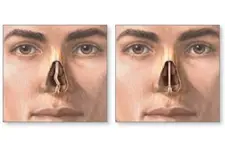

Kıkırdak Doku Çeşitleri Kıkırdak doku, bağ dokuları arasında yer alan, esnek ve dayanıklı bir yapıya sahip olan dokulardır. Farklı türleri ve işlevleri, vücudun çeşitli bölgelerinde önemli roller üstlenmektedir. Bu makalede, kıkırdak dokunun çeşitleri ve özellikleri detaylı bir şekilde ele alınacaktır. Kıkırdak Doku Türleri Kıkırdak doku üç ana türde sınıflandırılmaktadır: hyalin kıkırdak, elastik kıkırdak ve fibröz kıkırdak. Her bir tür, farklı yapısal özelliklere ve işlevsel amaçlara sahiptir.